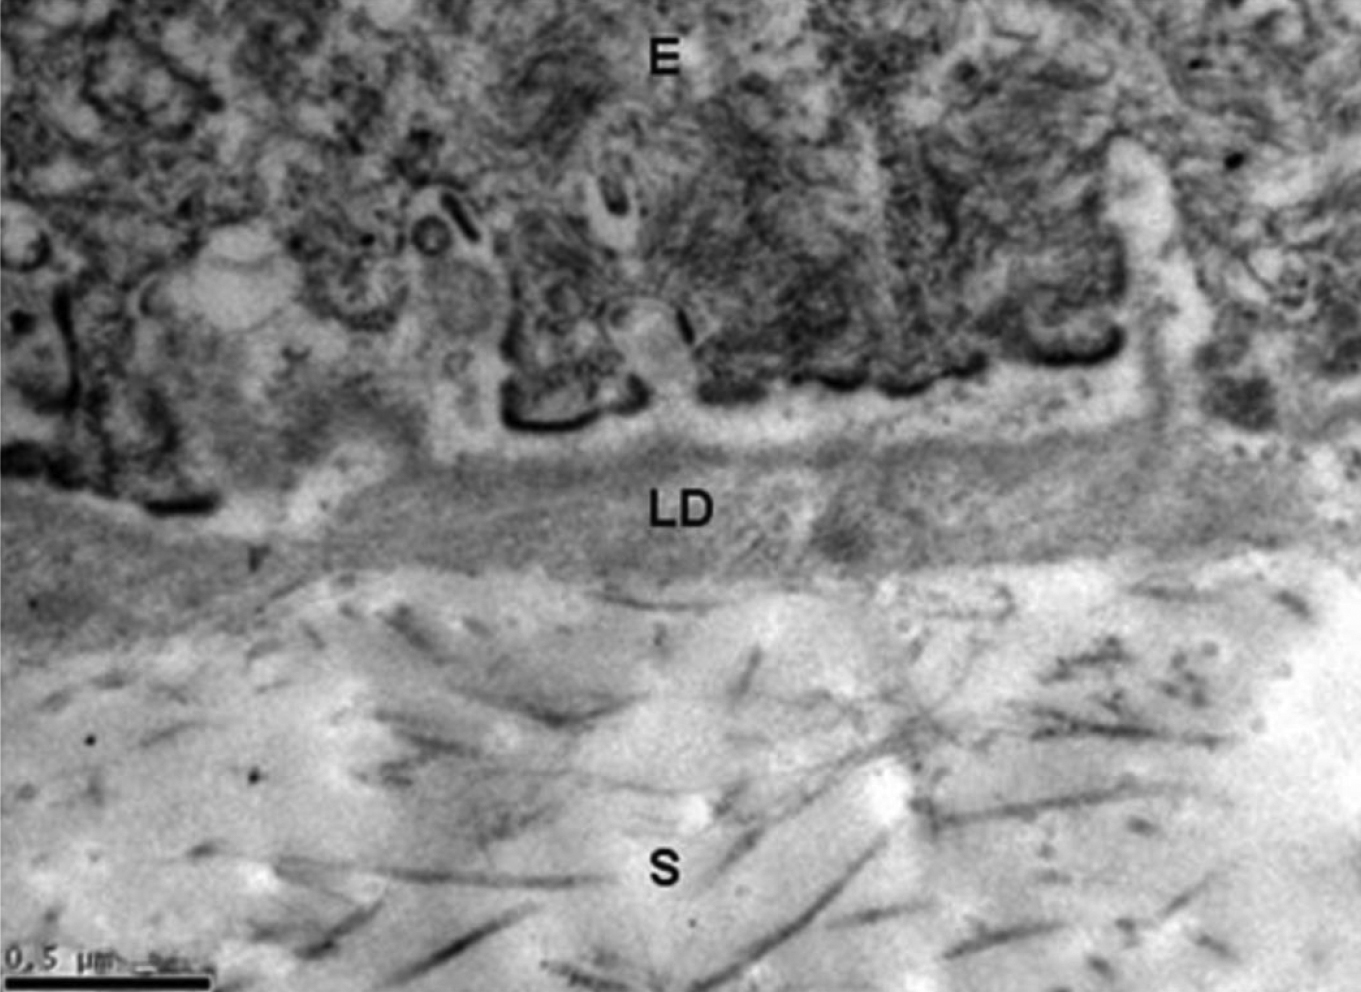

Figure 4. Transmission electron micrograph of untreated HAM tissue (normal control). The basement membrane supports the overlaying epithelium

and is composed of a three-layered basal lamina and lamina fibroreticularies. Lamina rara externa (lucida) is an electron-lucent

zone directly bordering the adjacent cell which makes up the upper portion of the basal lamina. Lamina densa (LD) is an electron-dense

zone that appears somewhat amorphous and granular, and constitutes the intermediate part of the basal lamina. Lamina rara

interna comprises the basal portion of the basal lamina. The three layers of basal lamina sit on top of the lamina fibroreticularies,

which is synthesized by cells from underlying connective tissue and contains fibrillar structures namely anchoring fibrils,

elastic fibrils and microfibril bundles. In the image, “E” indicates epithelium, “LD” indicates lamina densa, and “S” indicates

stroma. Magnification: 30, 000×, the scale bar indicates 0.5µm.